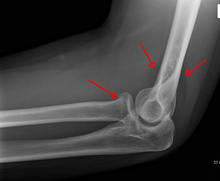

Fracture

Specific fracture types of the radius include:

- Essex-Lopresti fracture - a fracture of the radial head with concomitant dislocation of the distal radio-ulnar joint with disruption of the interosseous membrane.[4]

- Distal radius fracture

- Galeazzi fracture - a fracture of the radius with dislocation of the distal radioulnar joint

- Colles' fracture - a distal fracture of the radius with dorsal (posterior) displacement of the wrist and hand

- Smith's fracture - a distal fracture of the radius with volar (ventral) displacement of the wrist and hand

- Barton's fracture - an intra-articular fracture of the distal radius with dislocation of the radiocarpal joint.